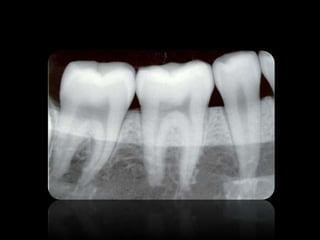

3.

• Las imagenes

son llamadas radio opacas. • Las imagenes son llamadas radio lúcidas.